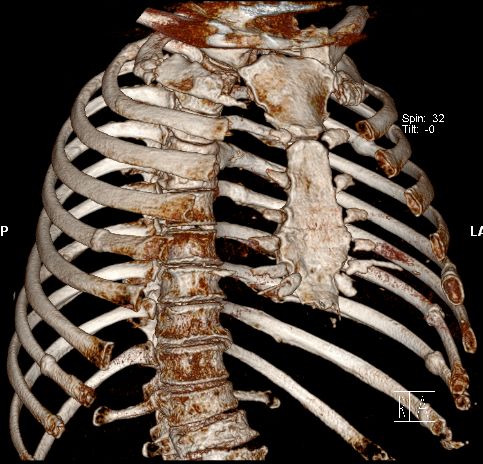

Rippen |

58-jähriger Mann mit Knochenmetastasen LWK3/4. PSA 911. Vor

einem Jahr Spondylodese LWK3-4. Bestrahlung. Jetzt Metastase BWK 6. Die

CT-Rekonstruktion zeigt zusätzlich mehrere Rippenmetastasen.![]() |

![]() | |||||||||||||||||||